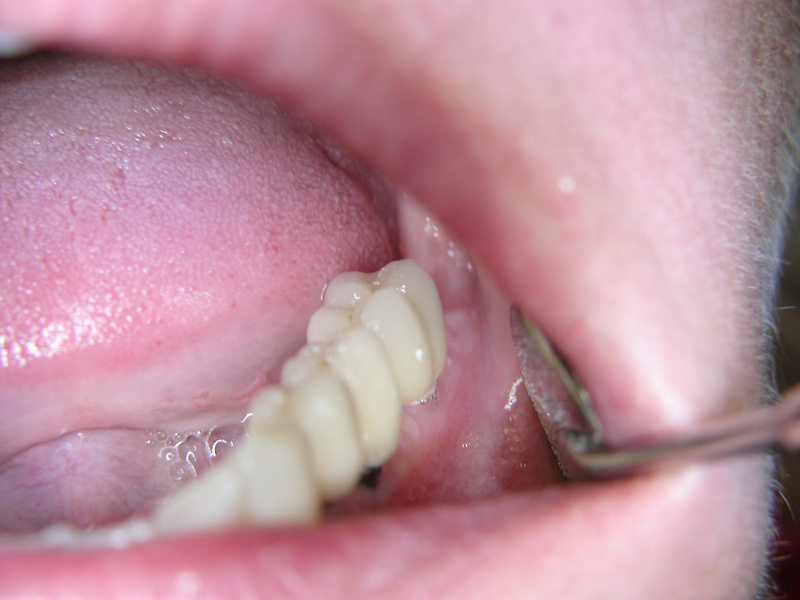

Implante - Galerie Foto

Caz II